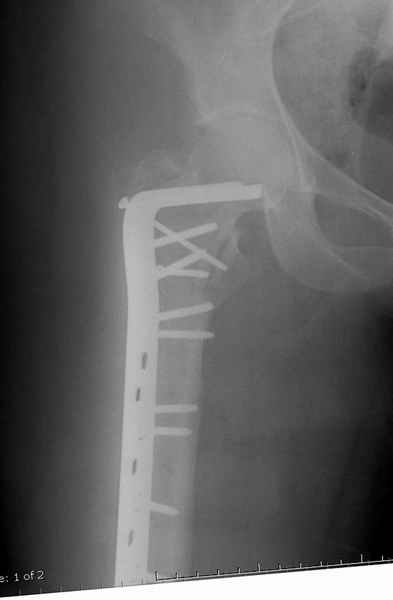

Postop Blade Fixation

Ap pelvis Rt sub-intra trochanteric Fracture, AP Rt hip, Postop Blade Fixation